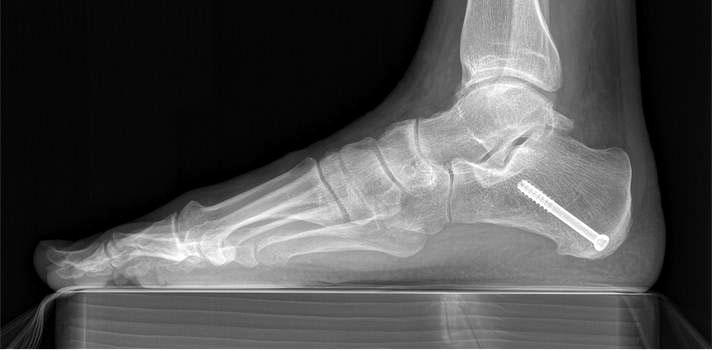

715.<br> Für die medialisierende Calcaneusosteotomie wird ein bogenförmiger Hautschnitt in Höhe des hinteren Fersenbeines gesetzt, die Subcutis bis zum Fersenbein durchtrennt und dieser bogenförmige Lappen nach ventral präpariert. Dadurch kommt es zu einem Schutz des Nervus suralis, welcher gemeinsam mit den Peronealsehnen nach vorne gehalten wird.<br> Es wird nun das Fersenbein mit einem Wundspreizer eingestellt und cranial sowie caudal mit 2 Hohmannhaken umfahren.<br> Dann wird das Fersenbein mit der oszillierenden Säge osteotomiert, mit dem Meißel und dem Wundspreizer distrahiert.<br> Danach wird das Fersenbein ca. 1 cm nach medial verschoben, unter Vermeidung der Cranialisierung des hinteren Calcaneus . Dann wird von dorsal über eine Hautstichincision der Bohrdraht für die 4,5mm (- 6,5 mm) kanülierte Schraube eingebracht und über die Osteotomie in den vorderen Calcaneusanteil vorgeschoben.<br> Kontrolle im Bildwandler in 2 Ebenen. Wenn die Bohrdrahtlage gut ist Überbohren für die kanülierten Schrauben und Eindrehen der Schraube. (Alternativ kann an Stelle der Schraubentechnik auch eine Fixation mit Stufenplatten oder Ähnlichem verwendet werden).<br> Wundverschluss am lateralen Zugang und über der Stichincision.</p>"> 715.<br> Für die medialisierende Calcaneusosteotomie wird ein bogenförmiger Hautschnitt in Höhe des hinteren Fersenbeines gesetzt, die Subcutis bis zum Fersenbein durchtrennt und dieser bogenförmige Lappen nach ventral präpariert. Dadurch kommt es zu einem Schutz des Nervus suralis, welcher gemeinsam mit den Peronealsehnen nach vorne gehalten wird.<br> Es wird nun das Fersenbein mit einem Wundspreizer eingestellt und cranial sowie caudal mit 2 Hohmannhaken umfahren.<br> Dann wird das Fersenbein mit der oszillierenden Säge osteotomiert, mit dem Meißel und dem Wundspreizer distrahiert.<br> Danach wird das Fersenbein ca. 1 cm nach medial verschoben, unter Vermeidung der Cranialisierung des hinteren Calcaneus . Dann wird von dorsal über eine Hautstichincision der Bohrdraht für die 4,5mm (- 6,5 mm) kanülierte Schraube eingebracht und über die Osteotomie in den vorderen Calcaneusanteil vorgeschoben.<br> Kontrolle im Bildwandler in 2 Ebenen. Wenn die Bohrdrahtlage gut ist Überbohren für die kanülierten Schrauben und Eindrehen der Schraube. (Alternativ kann an Stelle der Schraubentechnik auch eine Fixation mit Stufenplatten oder Ähnlichem verwendet werden).<br> Wundverschluss am lateralen Zugang und über der Stichincision.</p>" srcset="/assets/images/a/3-raswd6qgkh6s353.jpg 1x, /assets/images/g/3-exngvjjv83x827d.jpg 1.5x, /assets/images/w/3-836r57qt8j3eh0w.jpg 2x" width="270" height="240" loading="lazy">

Abbildung 3

Abbildung 4